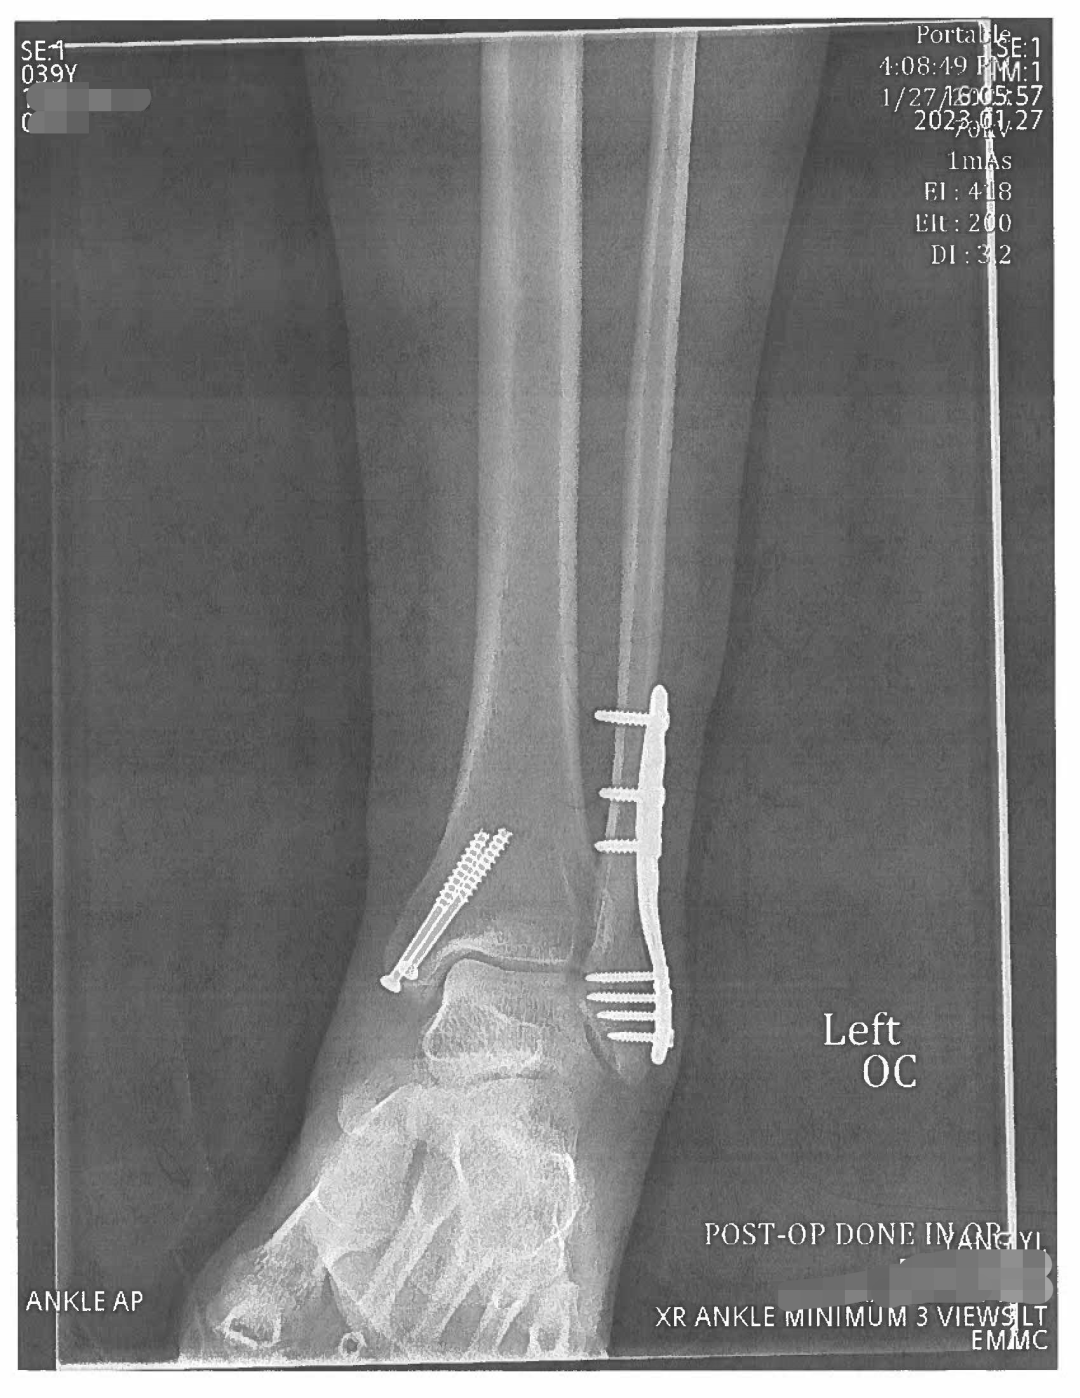

23:19PROMA案件小组成功与客户Y女士取得联系,获悉客户于2023113日前往美国班戈探望在美留学的儿子,127日晚从饭店返回住处途中,因地面结冰路滑不慎摔倒,随即前往当地Eastern Maine Medical Center紧急就诊。医院在经过X光等检查后确诊左脚踝骨折。经医院骨科会诊后于128日进行了相关钢钉固定门诊手术,辅以支具辅助。建议客户2周后(210日)复诊。